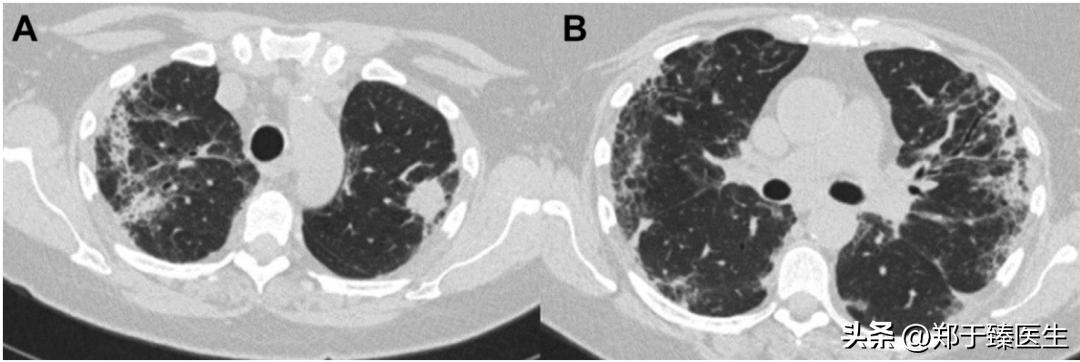

2022年,<Ann Thorac Surg>期刊刊载了一篇个案报道,详细展现了真实世界中关于手术决策的具体权衡。

这是一名中年女性患者,2021年1月初诊时发现左上肺2cm实性病变,符合肺癌特征。

但在术前检查时发现该患者感染了新冠病毒,因此,其手术被暂停。

此后,患者一度出现胸闷气促不适,但在社区医院的处理下逐渐好转,并在感染新冠病毒以后第6周复测核酸转阴。

此时重拍胸部CT,发现左上肺实性病灶较前增大,双肺仍有多发炎症表现。

最终在充分权衡手术利弊的情况下,为患者开展了微创条件下的亚肺叶手术,切除了左上肺的固有段,术后患者恢复顺利而出院。

从目前的研究结果来看,针对一个大于2cm的实性病灶,其标准治疗方案毋庸置疑,仍然是肺叶切除。

而这个病人左上肺的实性结节>2cm,最终只做了固有段切除,其背后更多地是对新冠病毒感染导致肺炎的妥协。